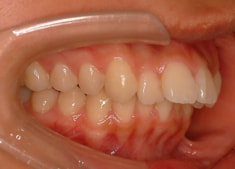

治療前